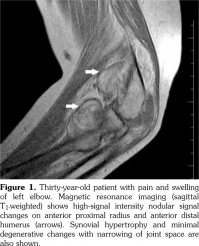

Magnetic resonance imaging of the left elbow (Figure 1) was performed and T1-weighted MRI showed high-signal intensity, while the short tau inversion recovery images showed isointensity with fat nodular signal changes on the anterior of proximal radius and distal humerus, respectively. MRI of the right wrist demonstrated synovial hypertrophy and effusion in the radioulnar and intercarpal joints. For exact diagnosis and treatment, open synovectomy of the left elbow was performed. Histopathological examination of the specimen (Figure 2) showed infiltration of the subsynovial space with mature adipocytes (hematoxylin and eosin stain x 40) and the diagnosis was reported as LA.

A soft tissue density might be seen on plain X-ray which is not diagnostic.(2) Although the characteristic image of MRI, particularly using fat-suppressed or short tau inversion recovery sequences, is diagnostic for LA; ultrasonography, computed tomography and arthrography have been used in diagnosis.(1,7,9) MRI findings include a synovial mass, fat signal intensity on all sequences, suppression of signal with fat-selective presaturation, joint effusion, and absence of MRI supporting hemosiderin.(1,9) As the synovial tissue may not be completely infiltrated by mature fat cells, atypical MRI findings may be seen.(4)